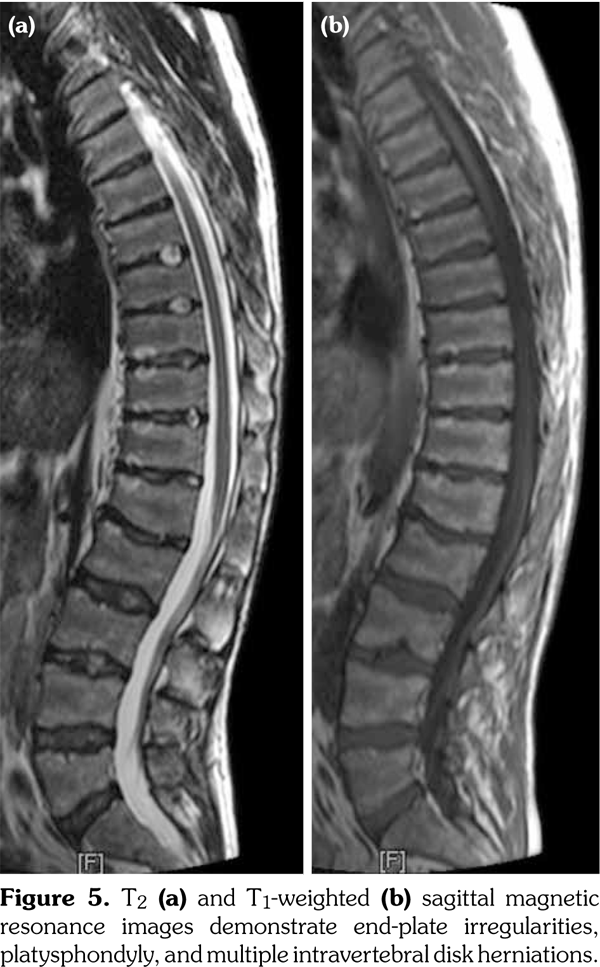

Radiographs of the hands showed enlargement of metaphyses, flattening of epiphyses, and narrowing of joint spaces with no erosions. Lateral radiograph of the foot revealed bilateral large ossified trigonum attached to the talus (mega os trigonum) (Figure 3). Radiographs of the spine showed increased kyphosis, generalized platyspondyly particularly at the thoracolumbar junction, and irregularity of the vertebral end- plates (Figure 4). Magnetic resonance imaging of thoracolumbar spine demonstrated irregularity in vertebral end-plates, multiple disk herniations, and platyspondyly (Figure 5). Dynamic contrast- enhanced magnetic resonance imaging of the wrist did not reveal any signs of synovial inflammation.

Clinical features of PPD have been described in several reports.(9-11) The radiographic features include varying degrees of epiphyseal involvement with enlargement of the epi-metaphyseal region, progressive joint narrowing, generalized platyspondyly, multiple intervertebral herniations, kyphoscoliosis, mega os trigonum and bone destruction with aging.(2,6,10) Our patient had progressive restriction of several joints, IP enlargements, dysplastic bone/cartilage changes, mega os trigonum and platyspondyly, with normal acute phase reactants. The presence of dysmorphic features and the absence of inflammatory signs should alert the physicians for the possible hereditary dysplasias like PPD.